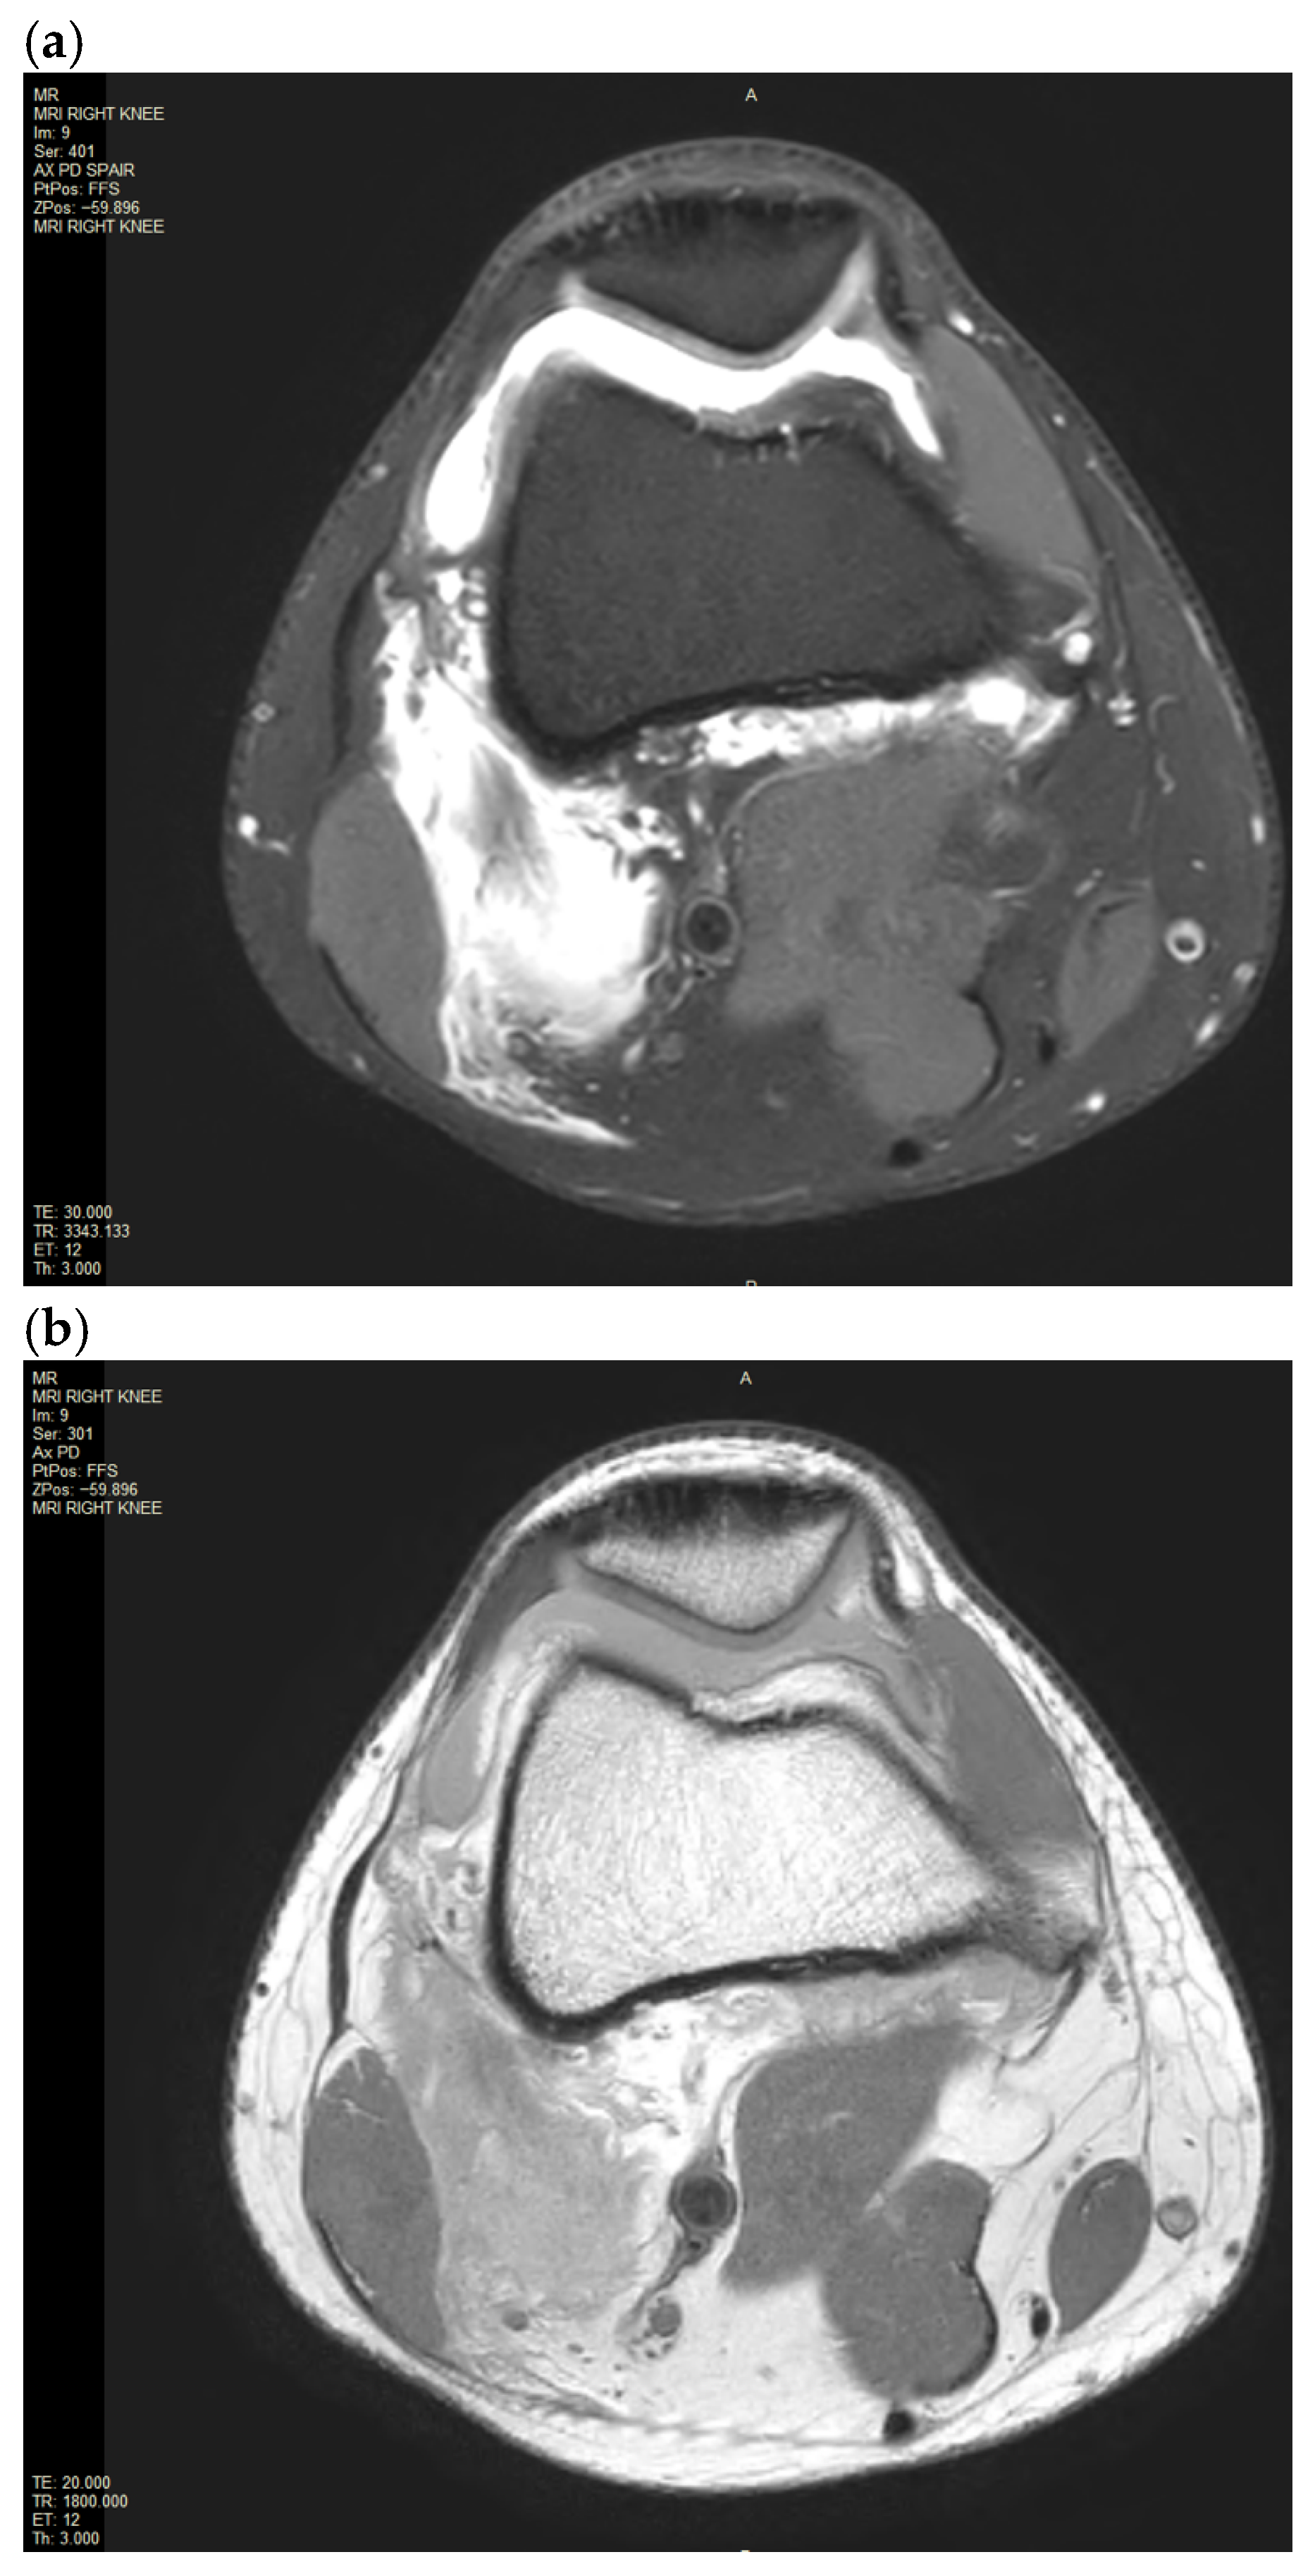

An X-ray of the right knee was initially performed to rule out a bony injury (Figure 1). The X-ray demonstrated marked soft tissue swelling of the knee joint with moderate effusion extending into the supra-patella recess. There was no evidence of acute or recent bony injury. The presence of radiological joint effusion raised suspicion for potential ligamentous or meniscal injuries. Subsequently, a magnetic resonance image (MRI) of the right knee was performed to further characterise the injury. MRI was obtained with a 1.5T Philips Achieva dStream MRI (Philips, Amsterdam, Netherlands) with Release 5.7 software. The routine knee protocol was performed, including sequences as follows: Axial Proton Density T2-weighted Turbo Spin Echo (Axial PD TSE), Proton Density Spectral Attenuated Inversion Recovery (PD SPAIR), Sagittal PD TSE, PD SPAIR, Coronal PD TSE, PD SPAIR (Figure 2a,b and Figure 3a,b).

The MRI of the right knee confirmed a moderate joint effusion extending into the supra-patella recess on the right with a focal intra-articular fluid located anterior to the tibial insertion of the ACL and posterior to the posterior cruciate ligament (PCL). The disrupted ACL fibres were displaced and concertinaed inferiorly. There was extensive pericruciate oedema around the expected position of the ACL. There was a focal bone oedema in relation to the central sulcus of the lateral femoral condyle. There was also partial avulsion of the medial gastrocnemius origin and incomplete avulsion of the lateral gastrocnemius origin. There was an extensive high fluid signal in the medial and lateral gastrocnemius origin at the posterior medial and lateral femoral condyle with an associated longitudinal tear. There were no injuries to the primary posterolateral corner structures, such as the lateral collateral ligaments or the popliteus tendon.

Figure 3. (a,b). MRI of the right knee image of the moderate knee joint effusion into the supra-patellar recess associated with incomplete avulsion of the lateral gastrocnemius origin as well as intramuscular haemataoma and partial avulsion of the medial gastrocnemius origin on Coronal PD PD SPAIR and PD TSE.